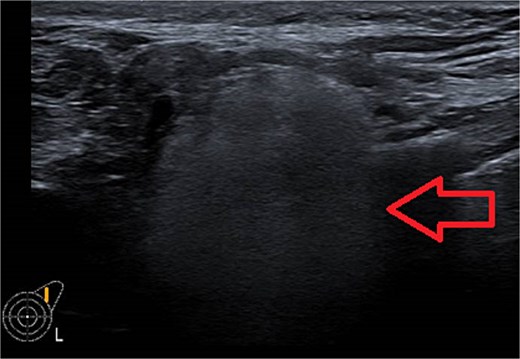

One week later, the patient reported a new lump in the left supraclavicular area. Examination revealed a 2 × 3 cm, nontender, mobile mass, confirmed by ultrasound to be silicone deposition (Figs 3 and 4). Increased breast swelling and lymphadenopathy were attributed to implant rupture and silicone migration.

Typical snowstorm appearance of supraclavicular silicone lymphadenopathy.